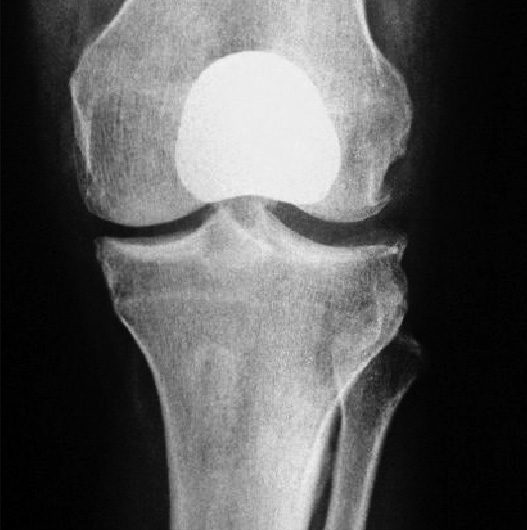

El reemplazo articular protésico de la rodilla consiste en el recambio de las superficies articulares del fémur, tibia y patela desgastadas y sin cartílago, por componentes metálicos que recrean la superficie de la articulación (tienen la misma forma) así como también la colocación de un espaciador de polietileno que permite crear una superficie de deslizamiento suave.

PRÓTESIS TOTAL

PRÓTESIS UNICOMPARTIMENTAL

PRÓTESIS PATELO-FEMORAl

PRÓTESIS DE REVISIÓn